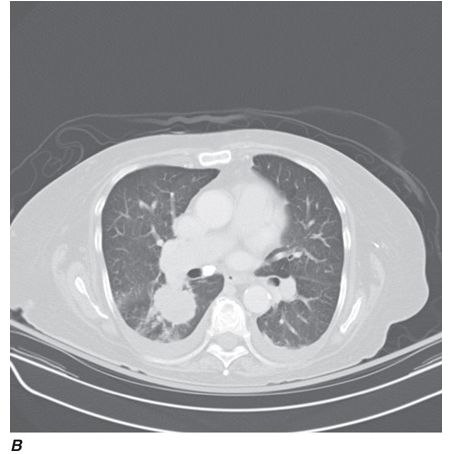

Computed tomography (CT) offers several advantages over routine chest radiography (Figs. C-1A, B and C-2A, B). First, the use of cross-sectional images allows distinction between densities that would be superimposed on plain radiographs. Second, CT is far better than routine radiographic studies at characterizing tissue density, distinguishing subtle density differences between adjacent structures, and providing accurate size assessment of lesions.

CT is particularly valuable in assessing hilar and mediastinal disease (which is often poorly characterized by plain radiography), in identifying and characterizing disease adjacent to the chest wall or spine (including pleural disease), and in identifying areas of fat density or calcification in pulmonary nodules (Figs. C-2A, B). Its utility in the assessment of mediastinal disease has made CT an important tool in the staging of lung cancer, as an assessment of tumor involvement of mediastinal lymph nodes is critical to proper staging. With the additional use of contrast material, CT also makes it possible to distinguish vascular from nonvascular structures, which is particularly important in distinguishing lymph nodes and masses from vascular structures primarily in the mediastinum, and vascular disorders such as pulmonary embolism.